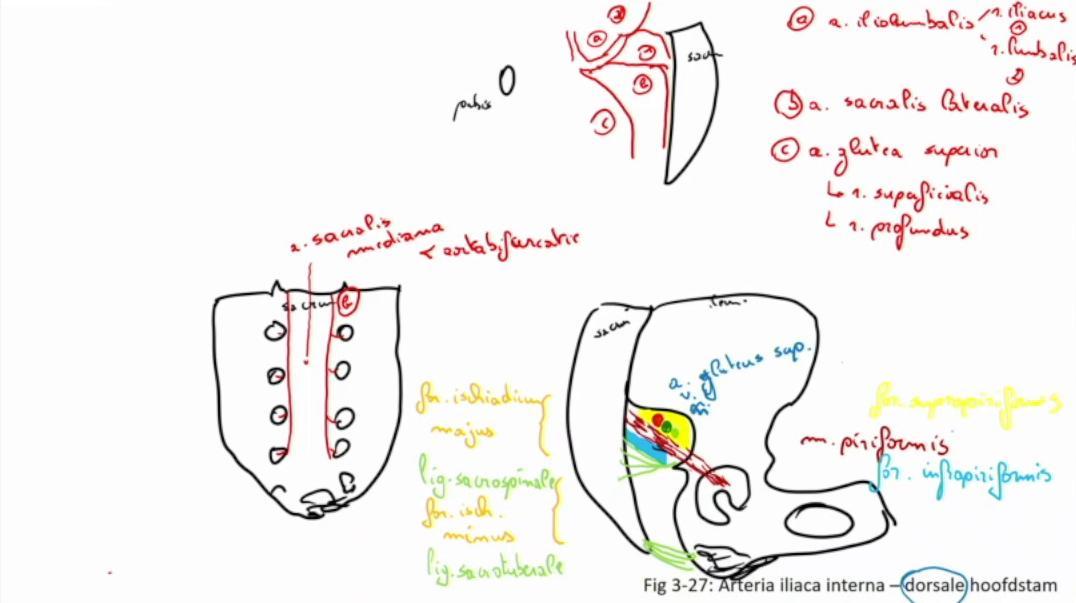

Fig 3.27: a. iliaca interna - dorsale hoofdstam

A doorsnede

os pubis sacrum -

a iliolumbalis

a sacralis lateralis -

a glutea superior

r superficialis r profundus

B vooraanzicht

C zijaanzicht

os coxae > os ilium lig sacrotuberale -

lig sacrospinale